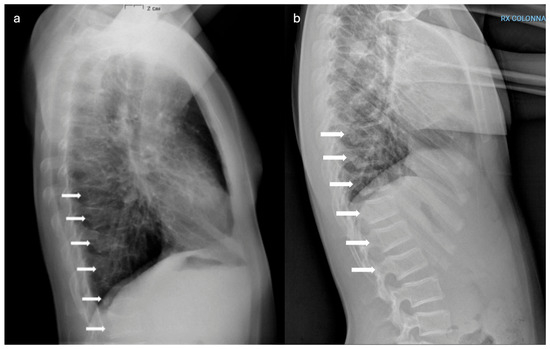

Hajdu–Cheney Syndrome in a Two-Generation Family: Longitudinal Skeletal Progression and Differential Therapeutic Responses in a Mother and Her Son

by Ruggero Lanzafame, Thomas Zoller, Angelo Pietrobelli, Giorgio Piacentini, Rossella Gaudino, Alessandra Guzzo, Giovanni Adami, Francesco Pollastri and Franco Antoniazzi

Hajdu–Cheney syndrome (HCS) is a rare genetic skeletal disorder caused by truncating variants of NOTCH2, characterized by progressive bone resorption and marked phenotypic heterogeneity. Despite advances in understanding Notch signaling in skeletal biology, longitudinal clinical data tracking disease evolution from early childhood through adolescence are lacking. Here, we report a rare longitudinal intrafamilial observation of HCS in a mother and her son carrying the same NOTCH2 pathogenic variant, providing novel insights into disease evolution and therapeutic response. Over extended follow-up, the son exhibited early vertebral fragility despite preserved or supranormal bone mineral density (BMD), whereas the mother developed severe osteoporosis, progressive acro-osteolysis, and multiple vertebral fractures. Longitudinal analysis revealed a dissociation between vertebral fragility and densitometric decline, challenging the paradigm that low BMD is the primary driver of skeletal morbidity in HCS. Treatment responses differed between the two patients, with bisphosphonate therapy in the son associated with stabilized BMD without altering vertebral structural progression, and denosumab in the mother associated with increased BMD, but not preventing progression of acro-osteolysis. Additionally, the emergence of extra-skeletal features during adolescence expands the phenotypic spectrum of HCS and suggests previously unrecognized systemic involvement. These data highlight intrinsic limitations of current therapeutic strategies and emphasize the need for targeted interventions addressing sustained Notch2 activation. Our findings contribute to the understanding of the natural history and therapeutic challenges of HCS, providing the framework for future mechanistic and translational research. Full article

Figure 1